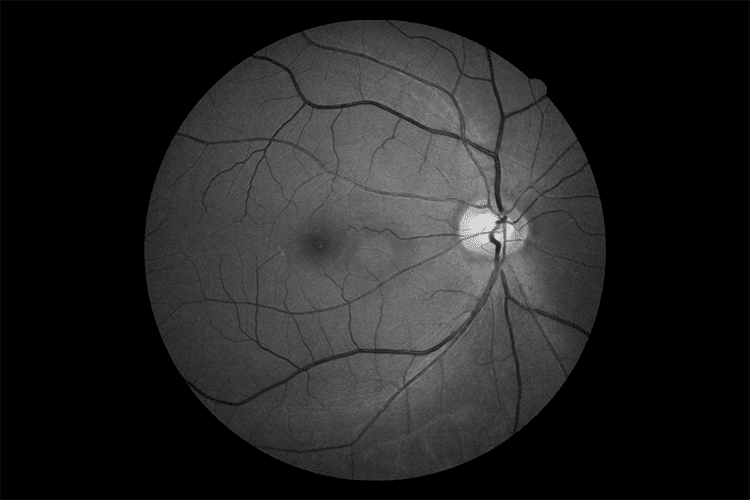

Вбудована цифрова ретинальна камера EOS 32,5 МП

Вбудована в OCT-R1, ретинальна камера тепер є частиною оптичної системи, яка ще більше покращує якість отриманих зображень сітківки. Удосконалена технологія Canon EOS Retina, інтегрована в OCT-R1, покращує діагностичні можливості та результати для пацієнтів завдяки функції повного автофокусування та зйомки при оптимізованому спостереженні за світлом та інтенсивністю спалаху.

Технологія Canon Opacity Suppression

Цей унікальний і складний програмний інструмент відновлює початкову яскравість і колір сітківки. Технологія зменшує несприятливий вплив помутнінь очей, таких як катаракта, для більш чіткого перегляду кровоносних судин, що призводить до того, що незрозумілі структури стають більш впізнаваними.

Цифрові фільтри

Цифрові фільтри REDFREE і COBALT забезпечують чудову якість зображення, порівнянну з оптичними фільтрами, завдяки процесору зображень DIGIC, який використовує спеціальні алгоритми для забезпечення оптимальних параметрів зображення реальних кольорів для зображення сітківки.